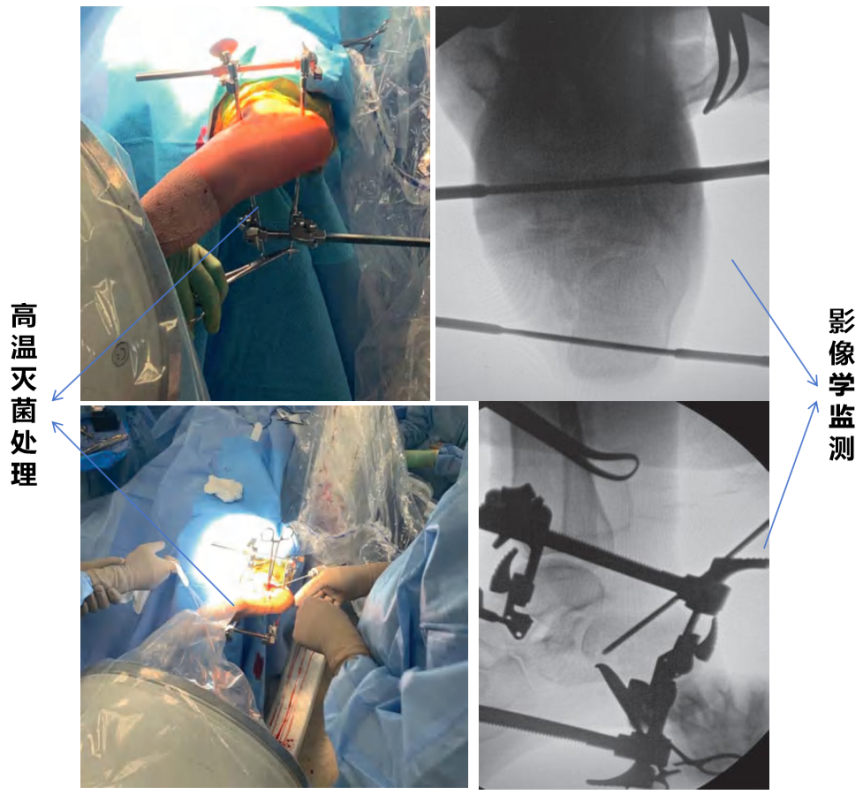

手术过程中,严格的无菌操作是预防感染的关键。医护人员会对手术区域进行彻底消毒,手术器械也会经过高温灭菌处理。在植入钢针和安装支架时,医生会借助影像学设备实时监测,确保钢针精准植入骨骼,避免因位置偏差导致的固定不稳。对于复杂的骨折,还会采用微创技术,减少对周围软组织和血管的损伤,保护骨折部位的血液供应(图7)。

图7.术中无菌操作与精准固定示意图